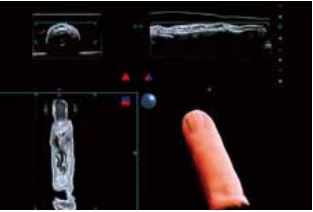

Пальці

На Рис.4 показані зображення нормального пальця. Кровоносні судини, кістки і нігті можна чітко розпізнати за допомогою Smart Sensor 3D (рис. 4а). Shadow Glass також виявився корисним в ортопедичних обстеженнях, наприклад, для візуалізації переломів. Зображення Shadow Glass можуть бути клінічно кориснішими, ніж звичайні зображення, оскільки на одному зображенні можна отримати більше інформації.

Крім того, використання вигнутої С-площини, створеної OmniView (рис. 4б), дозволяє зобразити кровоносні судини в пальцях безперервно. Таким чином, цілісність кровоносних судин можна оцінити, використовуючи як 3D Shadow Glass (рис. 4в, г), так і 2D вигнуту С-площину. Планується, що ці зображення виявляться корисними в широкому спектрі клінічних досліджень, таких як мікрохірургія.

a) Багатоплощинна реконструкція (MPR) та яскравість

б) Вигнута С-площина (OmniView)

в) Shadow Glass: Долоня

г) Shadow Glass: Тильна

Рисунок 4. Нормальні пальці з використанням Smart Sensor 3D